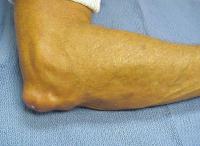

Subcutaneous calcification of the extensor surface of the elbow is common, and a common site for spontaneous drainage and infection.